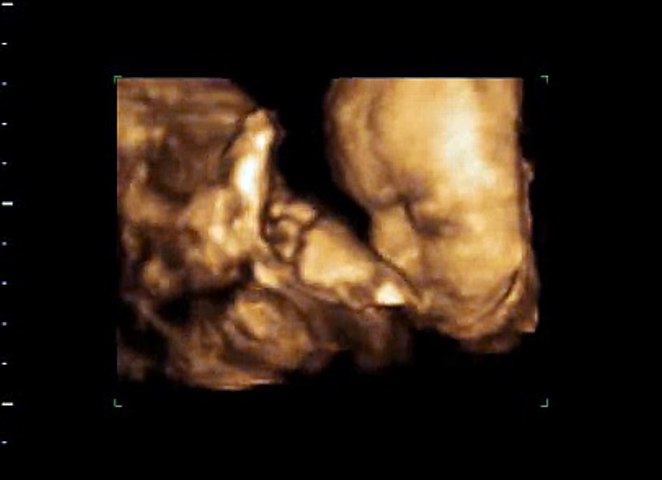

7 ssw ultraschall 3d. Dies war das Schönste was wir uns während der Schwangerschaft vorstellen konnten. With 3D Viewer unleash your imagination with our collection of animated models or view your own 3D model on file. Leider mit Nabelschnur vorm Gesicht daher nicht ganz perfekt darstellbar.

Und weil es so schön war nochmal. Aktion All-inclusive 20-30 Min 3D-BabyViewing Ultraschall inkl. Leider mit Nabelschnur vorm Gesicht daher nicht ganz perfekt darstellbar. Seems like its been widely supported for a while though. Schwangerschaftswoche lassen sich einige Entwicklungsstörungen erkennen und etwa ab der 14. About Press Copyright Contact us Creators Advertise Developers Terms Privacy Policy Safety How YouTube works Test new features Press Copyright Contact us Creators. Eindeutig ein Junge. 14ssw mit Zwerg Nr. SSW beginnt eine besonders aufregende Zeit.